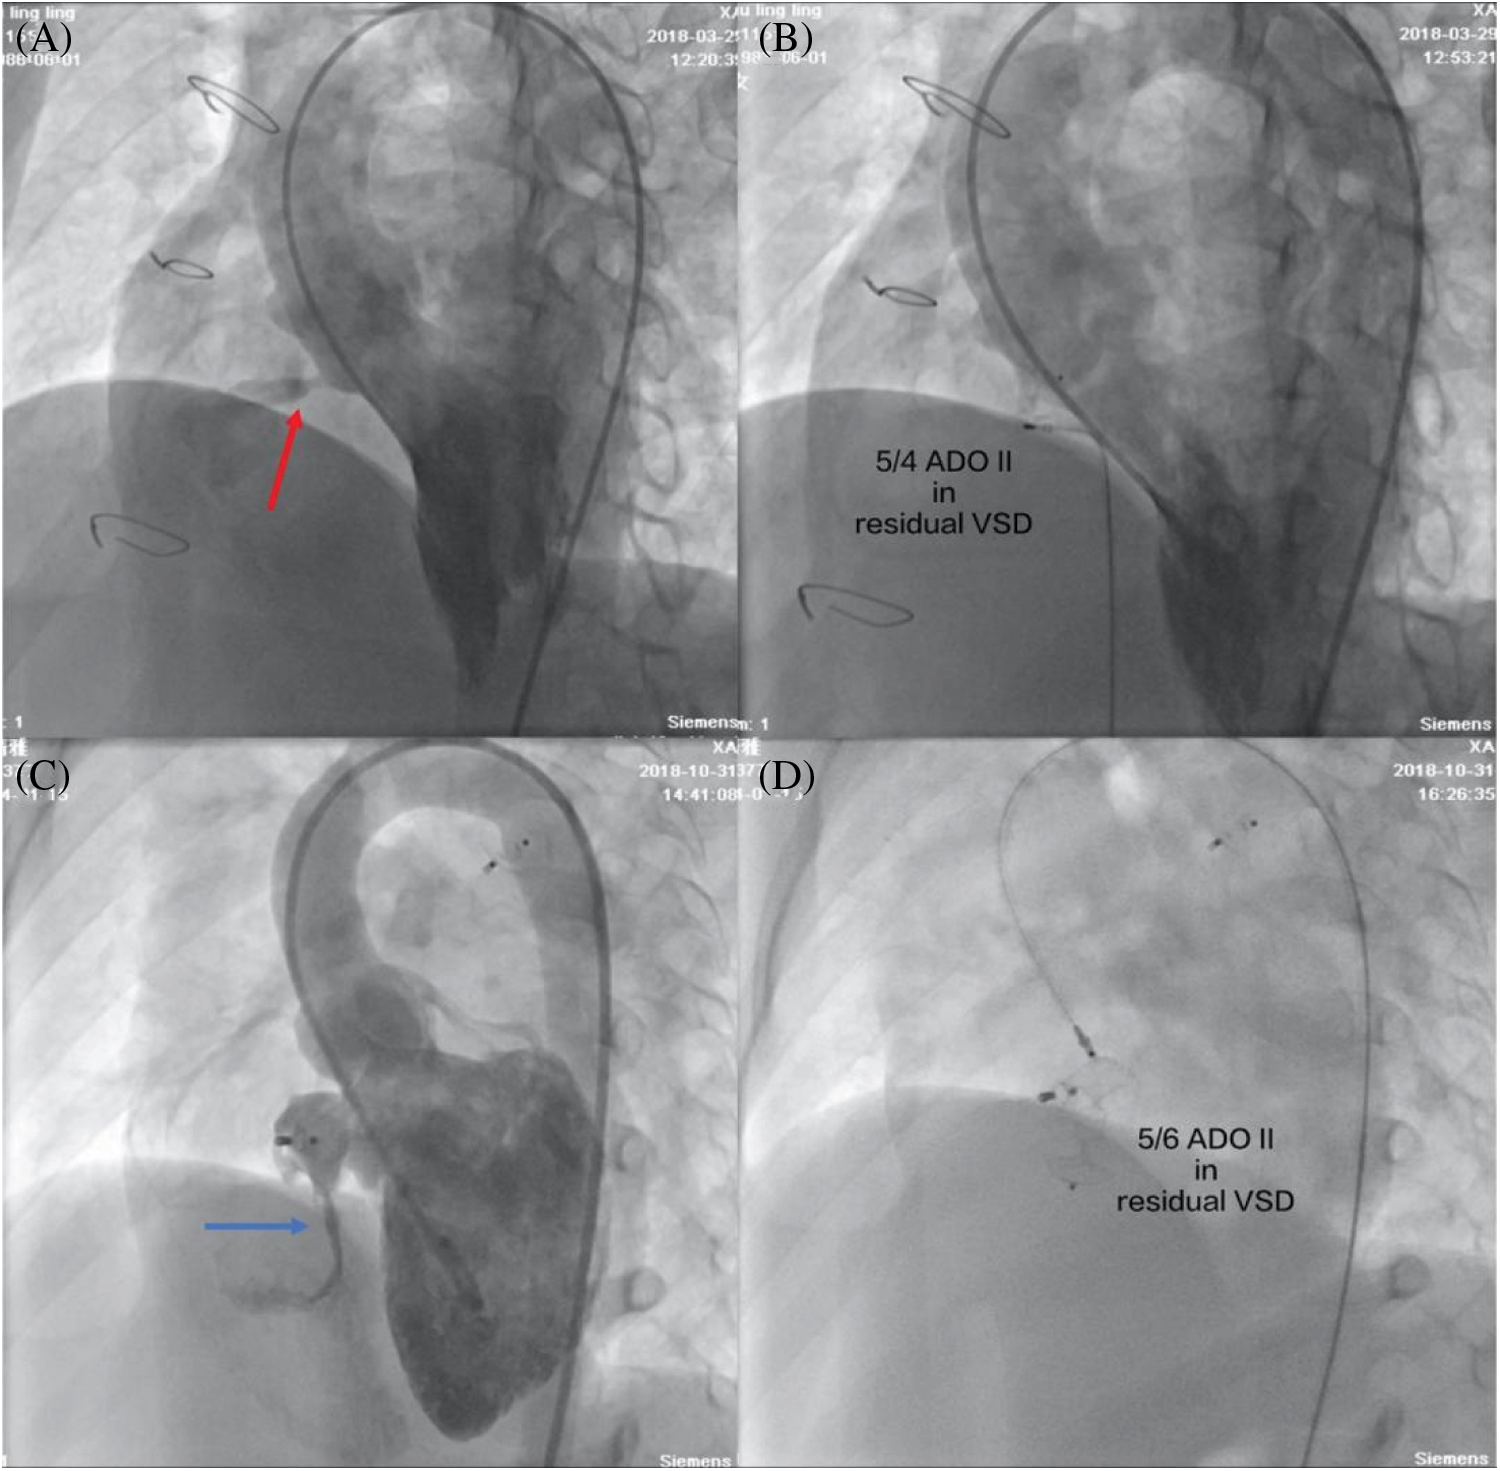

The type of device was changed to ADO II in 4 patients after the initial procedure. cAVB occurred in three pmVSD patients after the placement of a double-disk symmetrical concentric occluder, but they returned to normal sinus rhythm after retrieval of symmetrical device and then the closure was successful by implantation of an ADO II. One pmVSD patient with a double-disk asymmetrical occluder developed severe aortic regurgitation, and the subsequent use of an ADO II was successful in this patient. The overall immediate complete closure rate was 55.4%. All complex congenital cardiovascular malformations (ASDs and PDAs) were successfully simultaneously closed. In one 46-year-old man with aortic arch coarctation, a 5/4 ADO II occluder was successfully implanted into the intracristal VSD with mild aortic valve prolapse, and an aortic arch coarctation stent was simultaneously implanted. The ADO II was successfully implanted in all postsurgical residual and postclosure residual patients (Fig. 2).

Figure 2: Transcatheter closure of postsurgical residual shunts and postclosure residual shunts. (A) Left ventriculography showed a postsurgical residual shunt (red arrow); (B) No residual shunt was found with left ventriculography after a 5/4 ADO II occluder was successfully implanted; (C) Left ventriculography showed a postclosure residual shunt (blue arrow); (D) A 5/6 ADO II occluder was successfully implanted by a retrograde approach